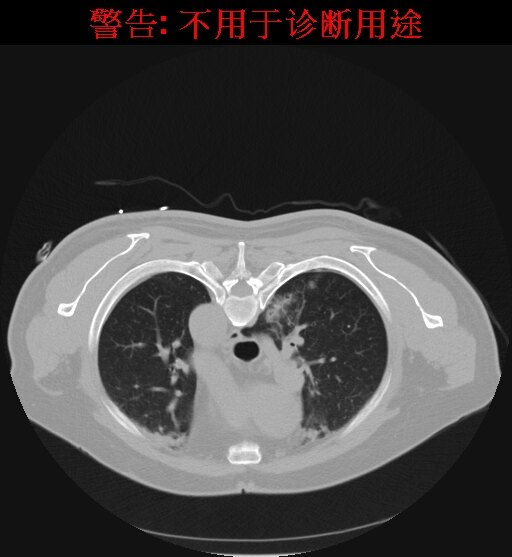

70岁老年男性患者,体积发现右肺上叶后段实性小结节,直径约8mm,边缘不规则,可见细小毛刺,随访观察体积较前增大,周围型肺癌可能性大,选择CT引导下微创射频治疗。

患者俯卧位,CT扫描定位肺小结节,规划穿刺路径,标记体表进针点并消毒,局部麻醉。